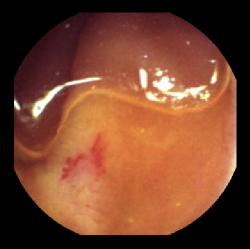

The RGB (Red, Green, Blue) endoscopic images are first converted into a colour space in which the components are de-correlated from the luminance component. Such colour spaces may include HSV (Hue, Saturation, Value) and CIELab colour spaces [5]. They are more near to the Human Vision System. The following figures show the colour transformation of an RGB endoscopic image to various colour components of the HSV and CIELab colour models.

(a) Original Image

Figure 1: Colour space transformation into HSV and CIELab